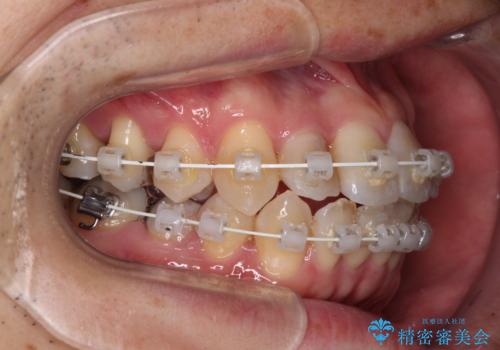

- 審美装置

- 治療期間

- 2年2ヶ月

舌の突出癖の影響か、下顎前歯がなかなか整わず、治療期間は予定よりも長期間となりました。

舌突出癖改善のトレーニングの重要性を認識することとなりました。